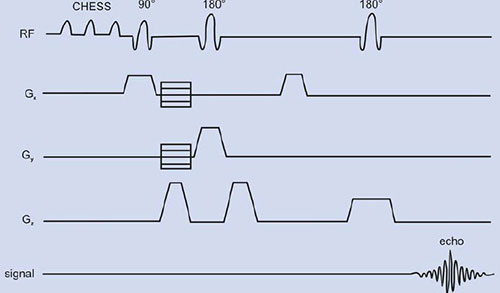

PRESS or double spin echo was proposed by two groups59, 60 is an adoption of the 1D DRESS technique to localization in 3D. For proton MRS, initially chemically shifted selective saturation (CHESS) pulses are needed to suppress the water resonance. Spatial localization is achieved by three frequency selective pulses applied in the presence of an orthogonal gradient (Fig. 1.11B). The localized VOI is at the intersection of the three orthogonal slices (Fig. 1.11A). The first 90° pulse is applied in the presence of gradient (e.g. along the x-axis) that selects a slice orthogonal to this axis.

Fig. 1.11: (A) A voxel that is defined by the intersection of three orthogonal planes (B) Timing diagram of a PRESS sequence. The initial CHESS pulses are to suppress the water signal. Slice-selective RF pulses excite three interacting orthogonal planes.

The magnetization of the selected slice is allowed to precess during TE1/4 and is refocused by a second pulse applied in the presence of a gradient along an orthogonal direction (e.g. the y-axis). At TE1/4 it refocuses the magnetization in a slice orthogonal to this axis. Finally, after a free precession delay TE2/4, a second refocusing pulse is applied in the presence of a gradient along the direction orthogonal to the first two directions (z-axis). This last pulse refocuses the transverse magnetization from a slice orthogonal to the first two slices. Therefore the acquired signal results from the volume element common to the three slices, producing a three-dimensional localization in one single scan. PRESS offers the important advantage of a factor of two gain in S/N, although signals are T2-weighted and J-modulated. The VOI definition and localization in PRESS are inferior to other sequences such as STEAM since the slice profiles of the 180° pulses are often worse than those of a 90° pulse. Further, the power requirement for 180° pulses is twice that of a 90° pulse, which may cause RF heating of tissues. Another disadvantage is the lengthened minimum echo time that is an important limitation for metabolites with short T2.